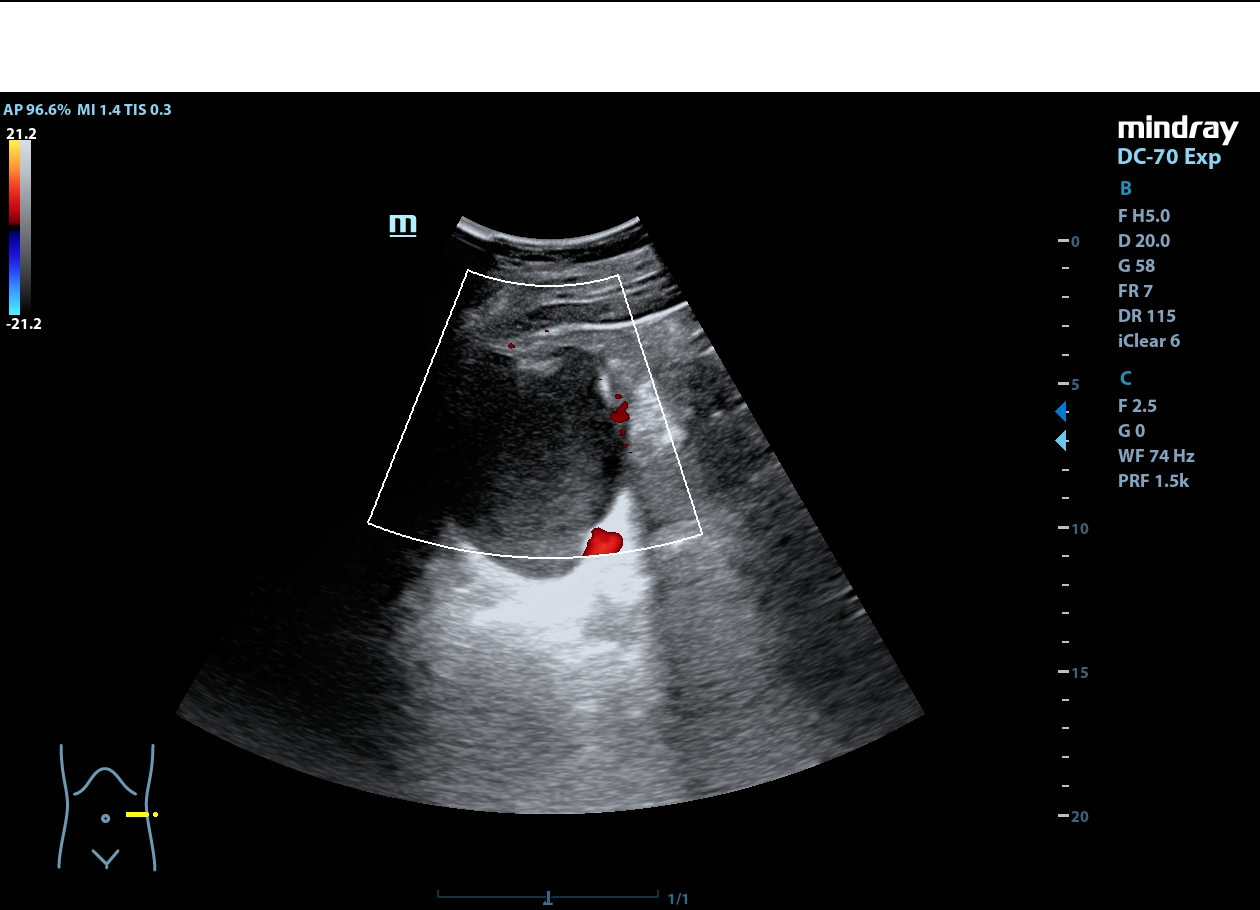

Descripción de los hallazgos ecográficos y las imágenes más relevantes para la resolución del caso

Riñón derecho de ecoestructura conservada, con dilatación pielocalicial grado I. Riñón izquierdo con adelgazamiento cortical y ureterohidronefrosis grado IV, sin poder localizarse el origen de la obstrucción, ausencia de jet ureteral izquierdo. Hallazgos sugestivos de síndrome de la unión pieloureteral.